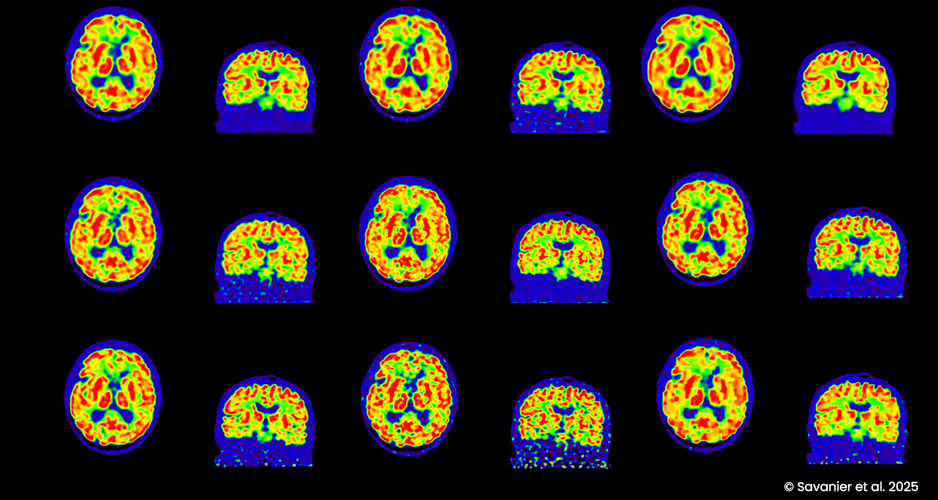

Une équipe de BioMaps, en collaboration avec le laboratoire de mathématique d’Orsay, a développé PET KinetiX, un logiciel qui permet de générer des cartes paramétriques de fonctions biologiques avancées à partir d’images TEP dynamiques. Ce type de logiciel pourrait contribuer à accélérer le transfert clinique de ces biomarqueurs TEP avancés en pratique clinique.